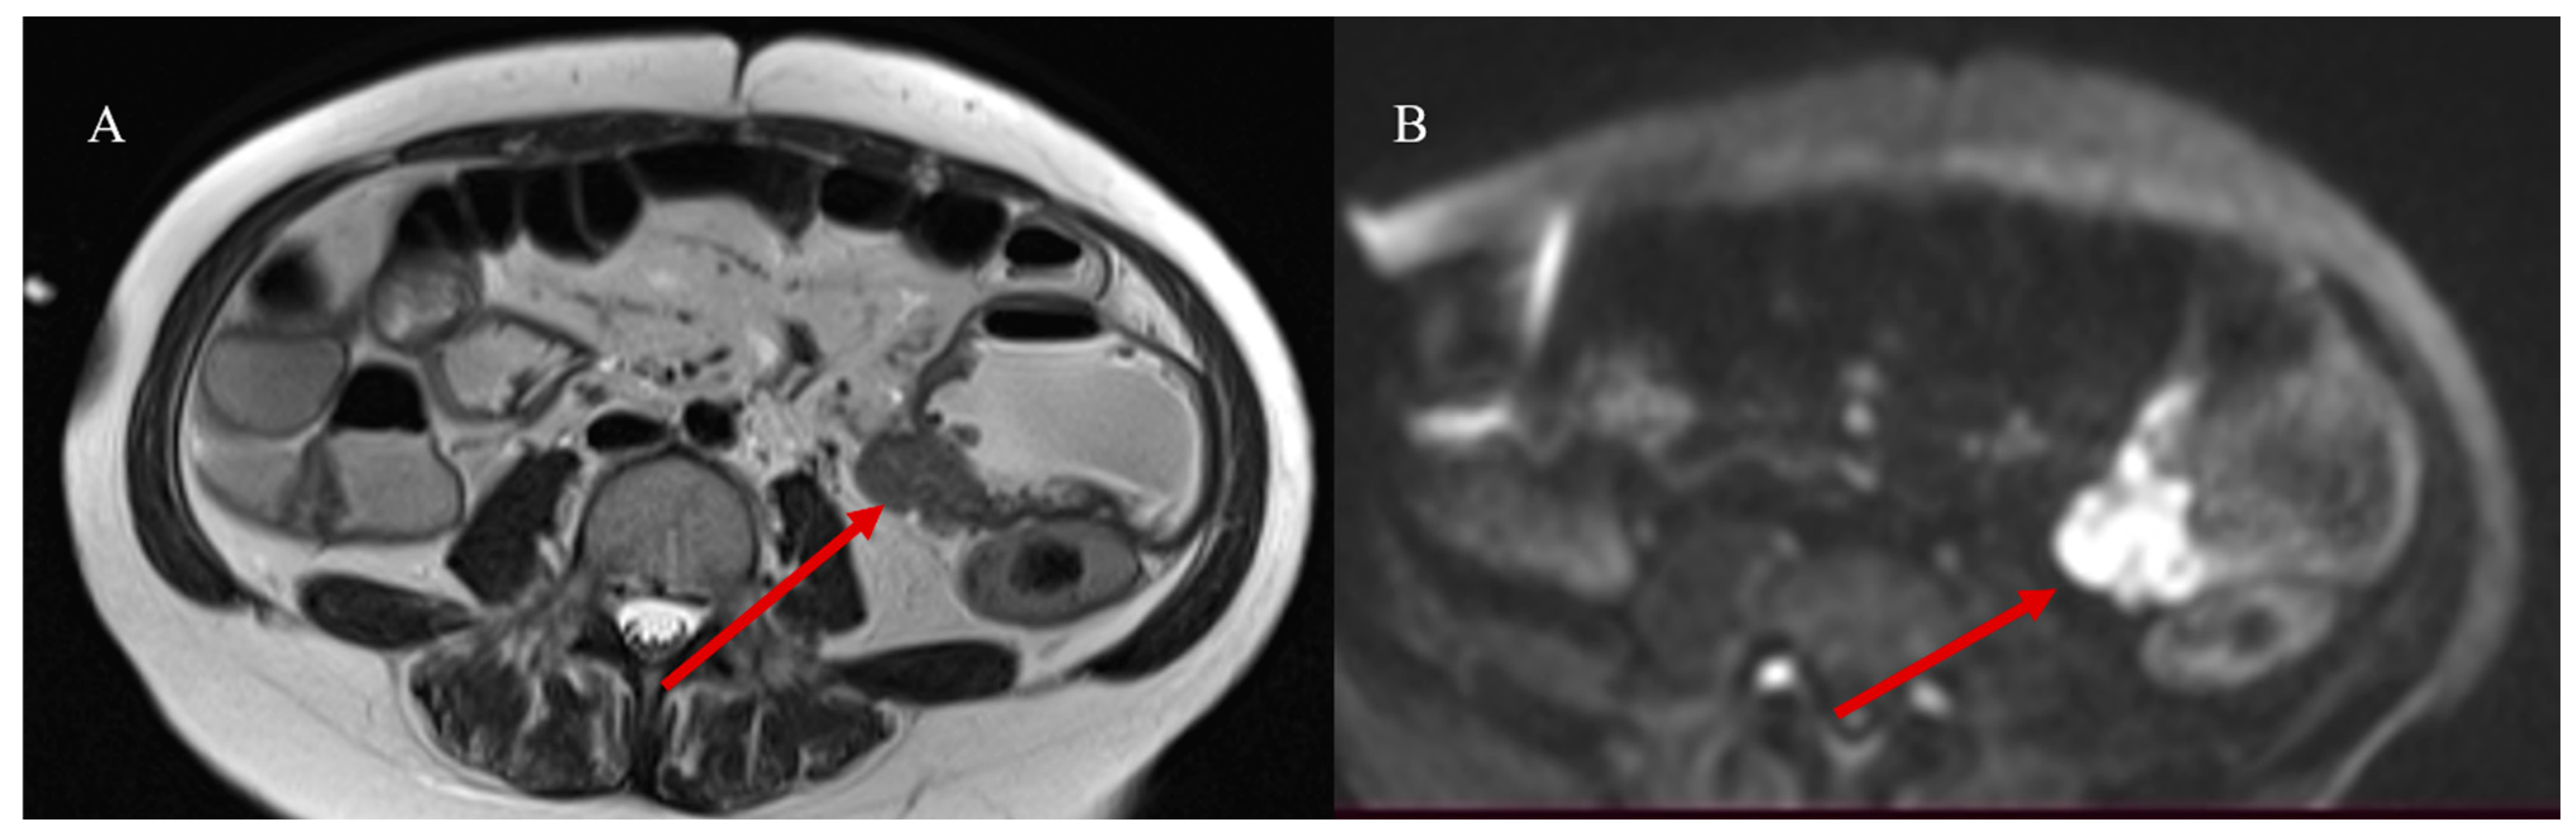

- Masselli, G.; Casciani, E.; Polettini, E.; Laghi, F.; Gualdi, G. Magnetic resonance imaging of small bowel neoplasms. Cancer Imaging 2013, 13, 92–99. [Google Scholar] [CrossRef] [PubMed]

- Faggian, A.; Fracella, M.R.; D’alesio, G.; Alabiso, M.E.; Berritto, D.; Feragalli, B.; Miele, V.; Iasiello, F.; Grassi, R. Small-Bowel Neoplasms: Role of MRI Enteroclysis. Gastroenterol. Res. Pract. 2016, 2016, 9686815. [Google Scholar] [CrossRef]

- Boone, D.; Taylor, S.A. Magnetic Resonance of the Small Bowel: How to Do It. Magn. Reson. Imaging Clin. N. Am. 2019, 28, 17–30. [Google Scholar] [CrossRef] [PubMed]

- Maccioni, F.; Busato, L.; Valenti, A.; Cardaccio, S.; Longhi, A.; Catalano, C. Magnetic resonance imaging of the gastrointestinal tract: Current role, recent advancements and future prospectives. Diagnostics 2023, 13, 2410. [Google Scholar] [CrossRef] [PubMed]

- Lu, J.; Zhou, Z.; Morelli, J.N.; Yu, H.; Luo, Y.; Hu, X.; Li, Z.; Hu, D.; Shen, Y. A systematic review of technical parameters for MR of the small bowel in non-IBD conditions over the last ten years. Sci. Rep. 2019, 9, 14100. [Google Scholar] [CrossRef]

- Pezzella, M.; Brogna, B.; Romano, A.; Torelli, F.; Esposito, G.; Petrillo, M.; Romano, F.; Di Martino, N.; Reginelli, A.; Grassi, R. Detecting a rare composite small bowel lymphoma by Magnetic Resonance Imaging coincidentally: A case report with radiological, surgical and histopathological features. Int. J. Surg. Case Rep. 2018, 46, 50–55. [Google Scholar] [CrossRef]